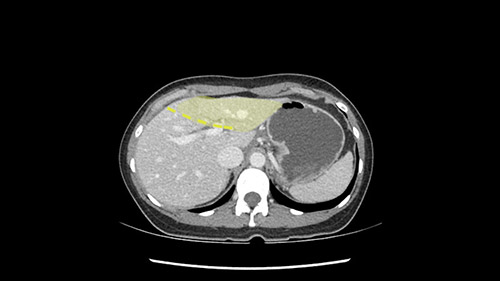

So if we look at the CT scan, on the axial, it’s a larger lesion. It’s about 6 or 7 or 8 centimeters. So it does look a bit threatening in terms of its resectability but if you really drill down deeply into the anatomy, and I think the coronal [imaging] is even better, you can see that the entire mass is on the patient’s left side of the falciform ligament. So it’s really only a left-sided tumor and not even really a left-sided tumor because Segment 4 is uninvolved anatomically.

None of the parenchyma is affected and this tumor is very exophytic; like many Hepatitis B hepatomas; and otherwise is resectable with either a wedge resection part of Segment 2-3 or a formal left lateral segmentectomy.

The tumor is so close to the falciform ligament, I had a question mark about the Segment 4b relation between segment 4b and segment 3. In a normal resection of segment 2 and 3, we would be keeping on the left side of the falciform ligament and start getting segment 3 and 2 portal pedicles but in here its getting so close. So oncologically, 4b should be checked during the OR.

What kind of procedure can we plan for this patient? It obviously has to be a left hemihepatectomy because most of the lesion is actually in Sg4. Can we do something which is less than a hemihepatectomy and just do only a segmental resection? The answer to that is that this vascular supply, if you are trying to ligate only the portal venous pedicle to the Segment 4, it is very close to the tumor and you will end up not having not a great margin as far as tumor resection is concerned so I would recommend a left hemihepatectomy and not just a partial or segmental resection. You can also see that it is crossing the falciform line and going on to Segment 2 and 3 so trying to do anything less than a left hemihepatectomy may not give the right kind of margins which we need for this tumor. Fortunately for us, the contours of the liver, which are very important to see in a Hepatitis B patient, there are no cirrhosis which I can see. The normal liver functions indicate that it's a well compensated Hepatitis B.

The other thing I would do in this case is to certainly to assess the coronal phase as we can see in the coronal phase, this tumor looks like it's growing from Segment 3, and again I don’t think there’s involvement of the right side of the liver or even on Segment 4.